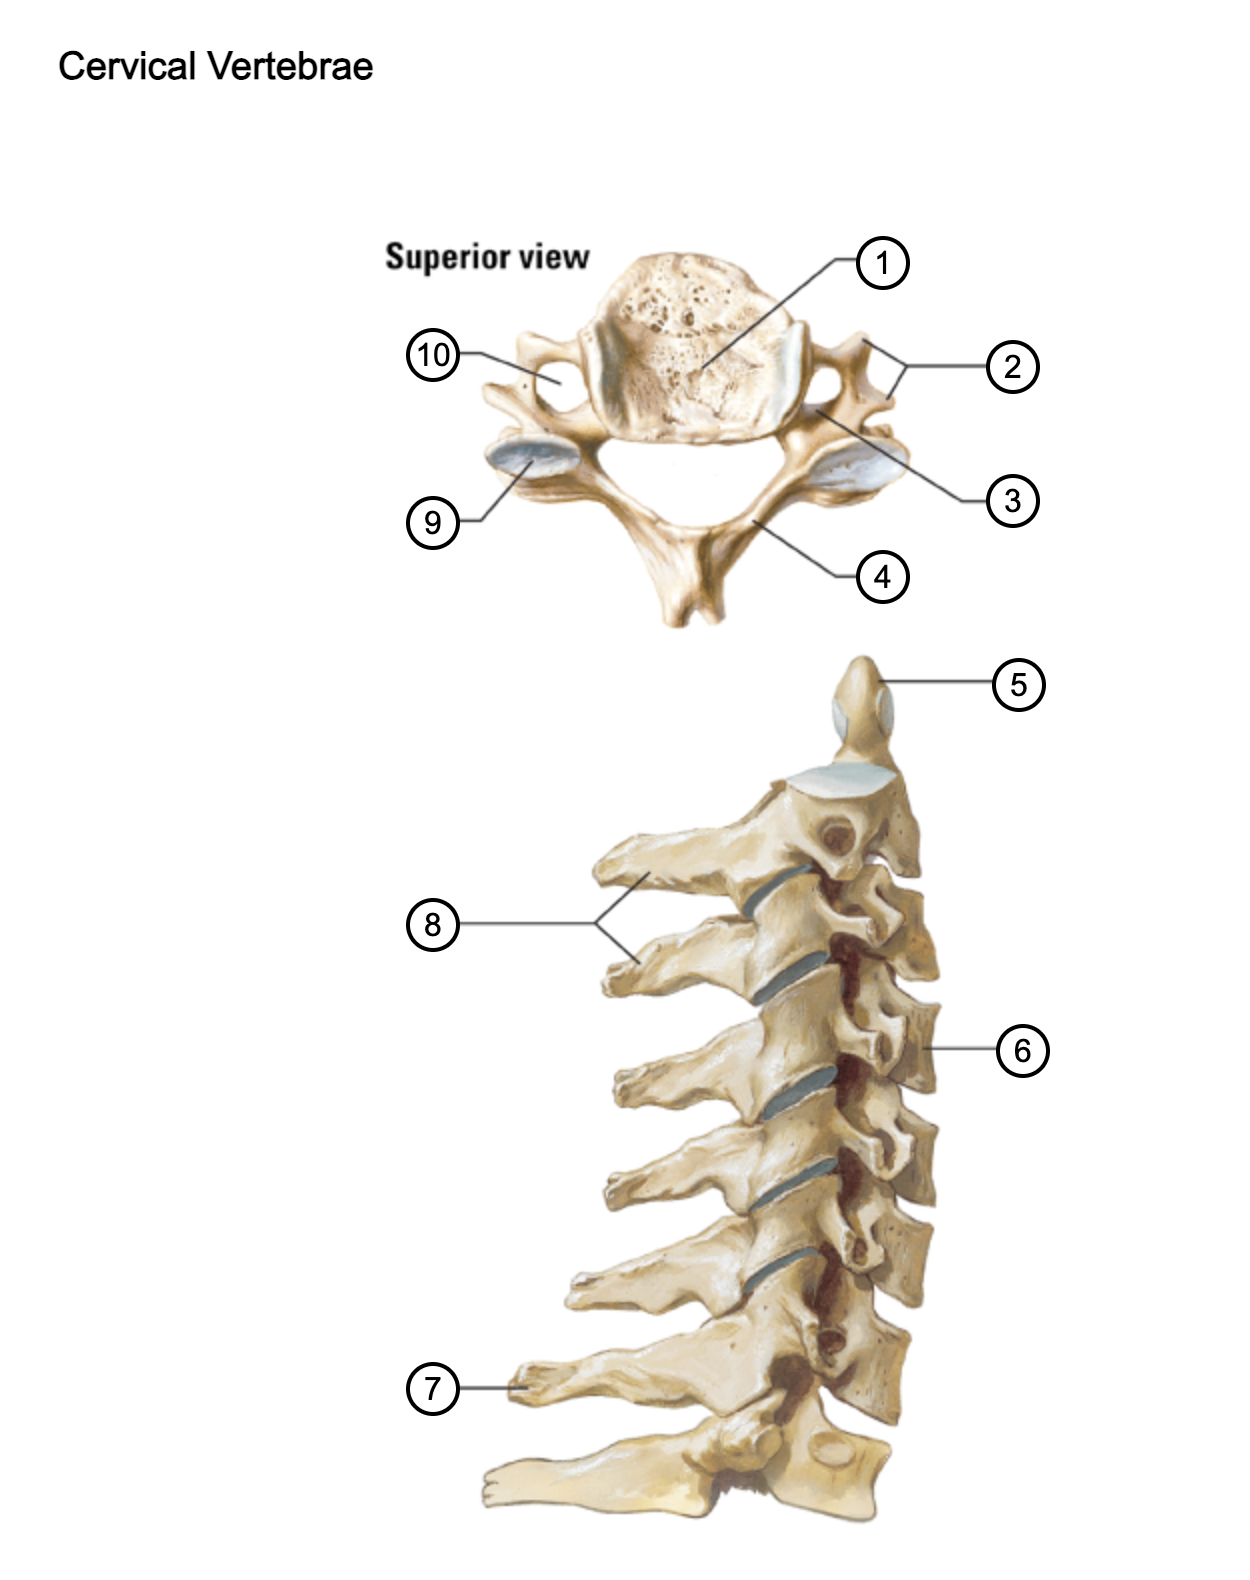

1

vertebral body

2

transverse process

3

pedicle

4

lamina

5

dens axis

6

vertebral body of C4

7

spinous process C7 (vertebra prominens)

8

spinous processes (C2 and C3)

9

superior articular process of C4

10

transverse foramen